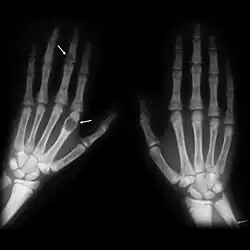

Bei langjährigem sekundärem renalen Hyperparathyreoidismus können in den Knochen sog. braune Tumoren auftreten, die aus knochen-abbauenden Zellen (Osteoklasten) und Bindegewebe bestehen. Die Bezeichnung brauner Tumor bezieht sich auf die braune Färbung, die von Einblutungen hervorgerufen wird.[23]

Knochen

Bei der feingeweblichen Untersuchung des Knochens finden sich Veränderungen, die als Ostitis fibrosa beschrieben werden. Der erhöhte Parathormon-Spiegel aktiviert Osteoklasten. Die vermehrte Osteoklasten-Tätigkeit führt zu einem Abbau von Knochensubstanz. Die feingewebliche Untersuchung zeigt Mikrofrakturen und Einblutungen. Es bilden sich Hohlräume, die gefüllt sind mit Bindegewebe, Osteoklasten und Hämosiderin-beladenen Makrophagen. Zunehmende Auflösung (Resorption) von Knochengewebe und bindegewebiger Umbau (Fibrose) führt zur Bildung von Knochenzysten, die mit bloßem Auge sichtbar sind. Bei weiterem Fortschreiten der Erkrankung verschmelzen die Knochenzysten zu braunen Tumoren, die braune Färbung ist Folge von Einblutungen und Hämosiderinablagerungen (Fallbeispiele und Abb. unter[51][52]).